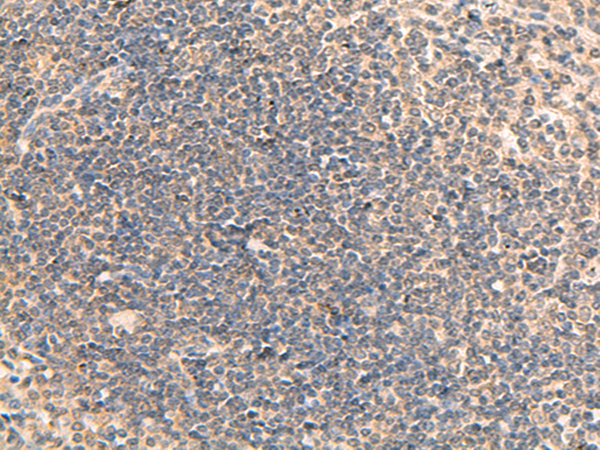

分类: 科研抗体货号: P10048别名: PP23; SOUL; C6orf34; C6ORF34B应用: IHC反应种属: Human, Mouse